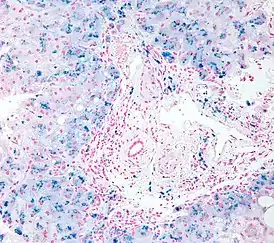

![]() Биопсия: гистологическая картина гемосидероза. | |